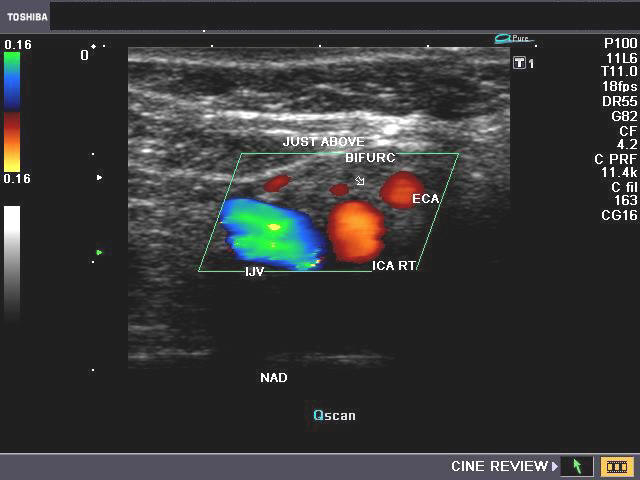

CAROTID Ultrasound examinations of the carotid arteries should include a minimum of the following images. -Longitudinal images of common carotid artery at its most proximal portion, including right ... Read Here